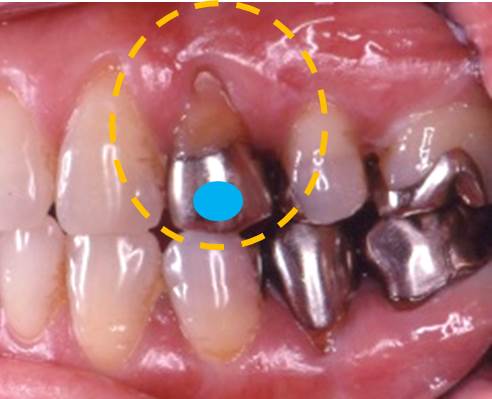

写真のオレンジ部分の歯茎が痩せてしまっています。

同じ写真ですが、「動かない歯茎」と「動く歯茎」の境界線をオレンジ線で示します。

歯周病治療を進めていく上で重要なのが「動かない歯茎(歯肉)」と「動く歯茎(歯槽粘膜)」です。歯の周りの「動かない歯茎」は、歯と付着することができます。しかしながら、歯の周りに「動く歯茎」しかない場合は、歯と付着することが出来ません。歯と歯茎が付着できた方が、歯周組織の健康は維持されやすいと言えます。

歯の周りの歯茎が動いてしまっては、歯周組織が安定しにくいのです。